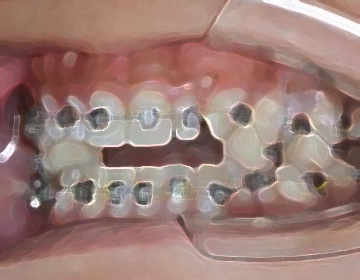

矯正治療では、歯並びを治すだけでなく、噛み合わせの改善によって3次元的顎の位置を修正し、

顎のバランスを整えることで全身のバランスを最良の状態へと導きます。

半調節性咬合器で噛み合わせ、CTで骨格のズレをチェックし治療計画を立案します。